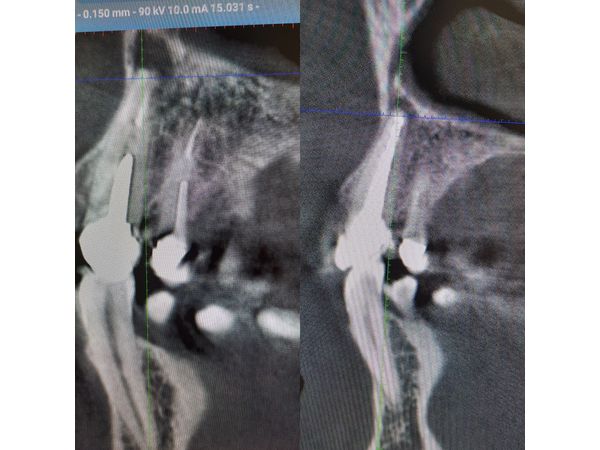

Компьютерная томография показала:

- корневой канал зуба 1.3 заполнен пломбировочным однородным материалом до самой верхушки;

- округлый очаг разрушения костной ткани с чёткими контурами с внешней стороны кортикальной пластинки.